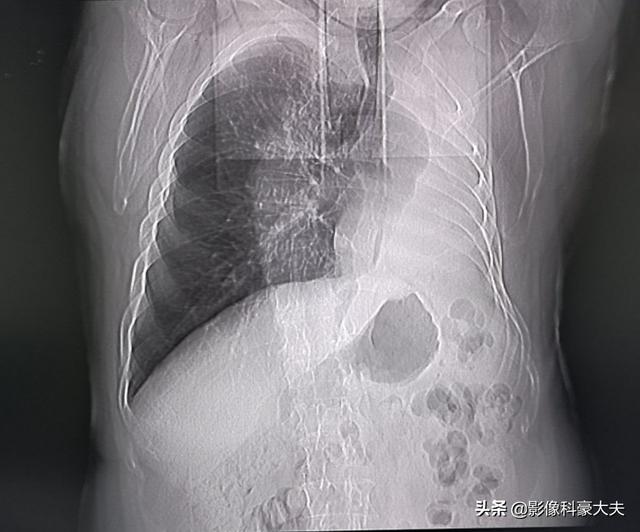

Eine sublobeare Resektion (d. h. eine segmentale Resektion oder Keilresektion) hat weniger Auswirkungen auf die Lungenfunktion, da weniger Lungengewebe entfernt wird und mehr normales Lungengewebe verbleibt. Wird eine Lobektomie durchgeführt, weil mehr Lungengewebe entfernt wird, verbleibt relativ wenig normales Lungengewebe, was sich stärker auf die Lungenfunktion auswirkt und eher zu Beschwerden in der Brust führen kann. Die folgenden Bilder zeigen die Lungen von zwei verschiedenen Resektionen: Das obere Bild zeigt die Lobektomie des rechten unteren Lungenknotens, und Sie können sehen, dass die rechte Lunge nach der Operation deutlich kleiner ist. Das untere Bild zeigt eine sublobar Resektion des linken unteren Lungenknotens, und Sie können sehen, dass die linke Lunge nach der Operation ein größeres Volumen aufweist.